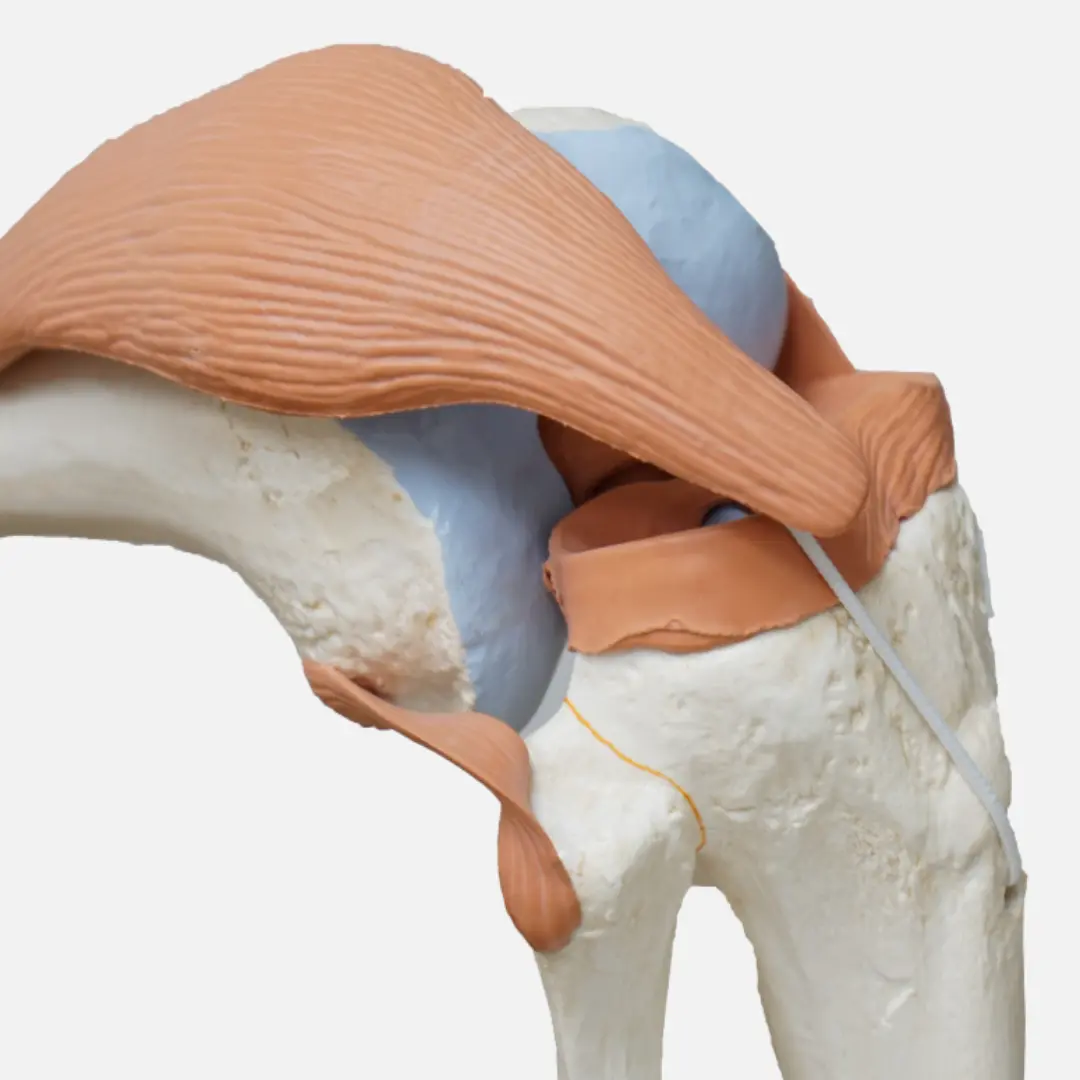

퇴행성관절염은 관절을 보호하고 움직임을 원활하게 하는 연골이 점진적으로 손상되거나 퇴행성 변화를 겪으면서 발생하는 만성 질환이에요. 연골은 뼈와 뼈 사이에서 충격을 흡수하고 마찰을 줄여주는 쿠션 역할을 하는데요. 나이가 들거나 과도한 사용, 외상 등으로 연골이 닳아 없어지면 뼈와 뼈가 직접 부딪히면서 염증과 통증을 유발하게 됩니다.

퇴행성관절염은 주로 무릎, 엉덩이(고관절), 척추, 손가락 끝마디 등 체중을 지탱하거나 많이 사용하는 관절 부위에 잘 발생해요. 관절염의 종류 중 가장 흔한 형태이며, 유전적 요인, 비만, 과도한 운동, 과거 관절 손상 등이 복합적으로 작용하여 발병합니다. 단순히 노화 현상으로만 볼 것이 아니라, 적극적인 관리와 치료가 필요한 질환이에요. 연골이 한번 손상되면 자연적으로 재생되기 어렵기 때문에, 초기에 증상을 인지하고 진행을 늦추는 것이 중요하답니다.